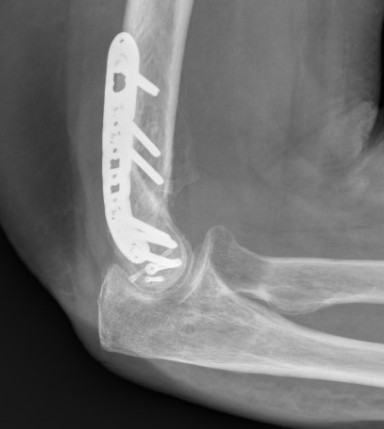

Lateral approach and ORIF

Technique

Arm on side table with tourniquet

- lateral approach centered on lateral epicondyle

- split extensor muscle

- open capsule and identify capitellum fracture

- reduce fracture

Usually AP headless compression screws (violates articular surface)

- +/- PA screws (risk AVN)

- +/- excise isolated cartilage lesions

- +/- postero-lateral plate